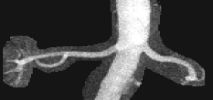

CE-MRA of the aortic arch and great vessels (left) into the brain, renal arteries (top), selective carotid bifurcation (top right) showing ICA/ECA stenosis, and 3-section run-off (very right) showing multiple stenoses, including long-segment bilateral SFA stenoses.